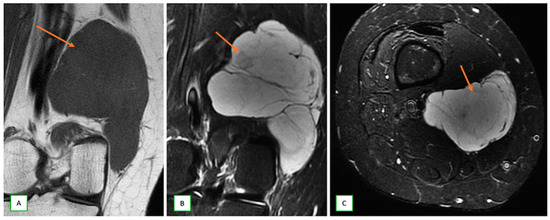

- Primary Sarcomas: Soft-tissue sarcomas are uncommon, accounting for just over 1% of adult malignancies. Synovial sarcoma, clear cell sarcoma, and epithelioid sarcomas are known to involve peripheral nerves. CT/MR reveals a large soft tissue mass with areas of necrosis or calcification and heterogeneous contrast enhancement. F-18 FDG uptake is useful for both tumor staging and treatment assessment (Figure 26, Figure 27 and Figure 28).